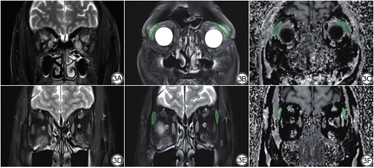

泪腺眶部及睑部在影像上不易区分,故在本研究中合并测量。首先,将扫描获得的MTI图像在Matlab软件(R2013b,MathWorks,美国)上通过标准公式(MTR=1-MT1/MT0)计算获得MTR[15]。MT1和MT0分别为施加和不施加预饱和脉冲获得的信号强度[15,21]。选取泪腺显示最大的层面,手动勾画泪腺全层感兴趣区(region of interest, ROI)(图1A),以获得平均MTR。同上,采用相同的方法在冠状位FS-T2WI图上勾画ROI,获得泪腺平均信号强度(图1B),并同时勾画同侧颞肌圆形ROI(面积为5~10 mm2),获得颞肌平均信号强度,从而计算SIR。所有定量参数均由两位从事头颈部影像诊断的医师独立测量,其中第1名医师(从事头颈影像诊断11年,主治医师)在1个月后再次测量,用以评估测量的观察者内一致性,第2名医师(从事头颈影像诊断4年,住院医师)与第1名医师的测量结果用以评估测量的观察者间一致性。取第1名医师的第1次测量结果纳入后续统计分析。

泪腺各定量参数测量的观察者内及观察者间一致性均为优(ICC:0.805~0.903)。活动期组泪腺MTR低于非活动期组,SIR高于非活动期组,两者差异均具有统计学意义(P<0.001,表1,图2)。活动期与非活动期TAO患者各一例影像图像见图3。